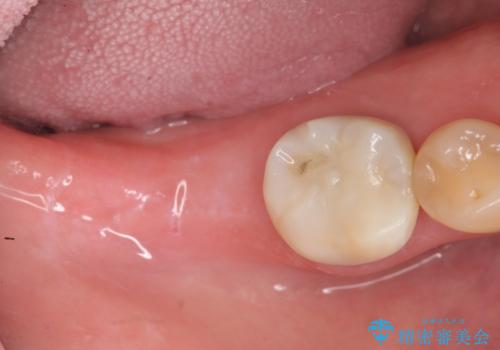

第二大臼歯は失ってしまうと咀嚼効率が10-30%程度低下してしまうと言われている、食事で物を噛み切るのに非常に重要な歯です。

失ってしまった奥歯をインプラントを用いて咬合機能回復することで、残っている他の歯を守ることにもなります。